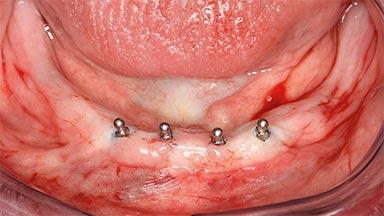

Four Immediately Loaded Mini-Implants Supporting a Mandibular Overdenture

# of Implants 4

Type of Implants One-Piece|Reduced-Diameter

Modality 3 or 4 interforaminal implants